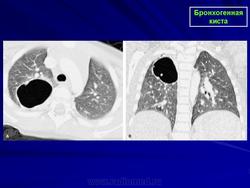

Рентгенологическая картина. При кисте, заполненной жидкостью, обнаруживается округлое или овальное затенение с четкими контурами. Контуры затенения могут изменяться в зависимости от фазы дыхания. При бронхогенной кисте, заполненной воздухом, видна правильной формы полость с чрезвычайно четким контуром, на фоне которой легочный рисунок обычно ослаблен. Более отчетливо просветление прослеживается на томограммах. Небольшой уровень жидкости на дне наблюдается не всегда, однако этот симптом, весьма важен с точки зрения дифференциальной диагностики истинных бронхогенных кист, продуцирующих секрет, от воздушных полостей другого происхождения (булл). Бронхография. Контраст не всегда попадает в полость из-за чрезвычайно узкого сообщения последней с просветом бронхиального дерева.

ID: 22985 Bronchogenic cyst Dr Mostafa Mahmoud El Feki - 10 May 2013 Features consistent of bronchogenic cyst. Differential considerations in...

ID: 8561 Bronchogenic cyst Dr Frank Gaillard - 11 Feb 2010 Chest x-ray of a 40 year old woman demonstrates a founded well circumscr...

ID: 9372 Bronchogenic cyst Dr Hani Alsalam - 9 Apr 2010 4 year old female patient with bronchogenic cyst.

ID: 10946 Bronchogenic cyst Dr Gagandeep Choudhary - 3 Oct 2010 CT through the chest demonstrates a large fluid density cystic structure...

ID: 6313 Bronchogenic cyst Dr Frank Gaillard - 4 Jun 2009 Retrocardiac bronchogenic cyst only well seen on AP CXR with expiration.